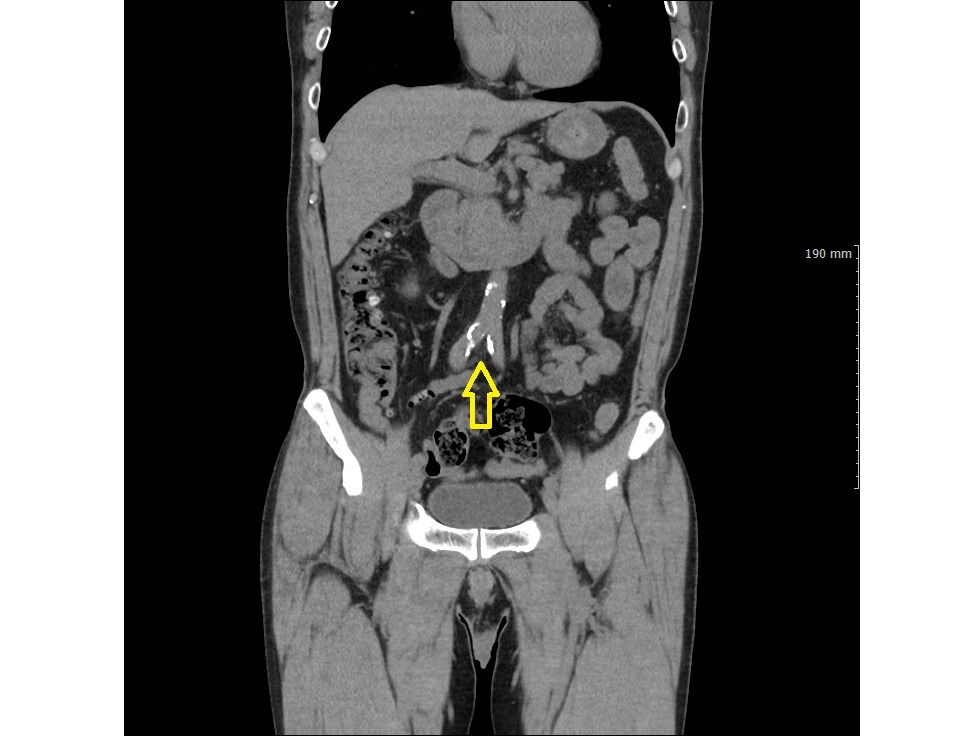

정맥돌 2.jpg 노란 화살표가 가리키는 것이 전립선 주변 정맥 혈관총내에 있는 정맥돌들